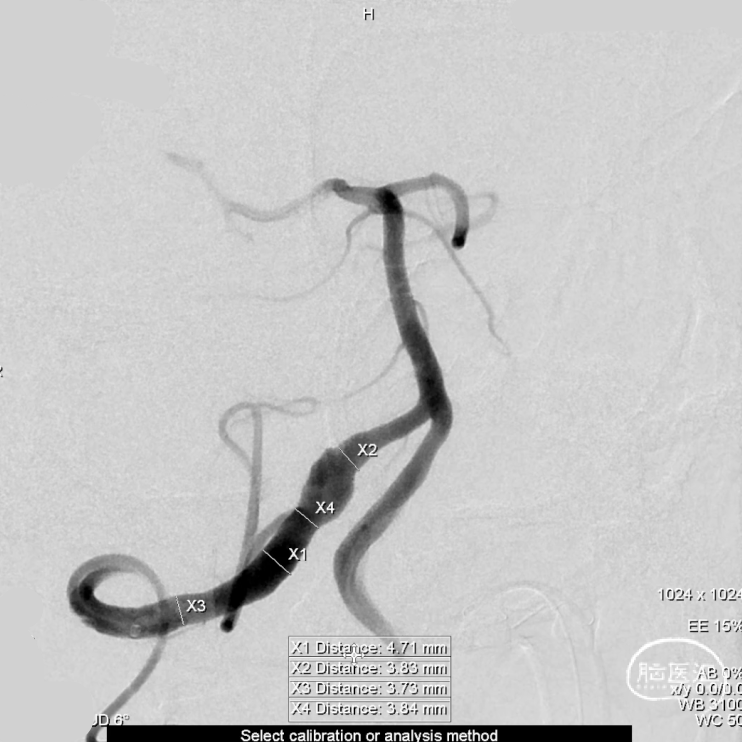

术前测量:

覆盖长度:49mm

直径:

远端锚定点:4.47mm

瘤颈远端:4.52mm

瘤颈近端:4.51mm

选择Lattice血流导向密网支架

5.3mm*41mm,9个球囊